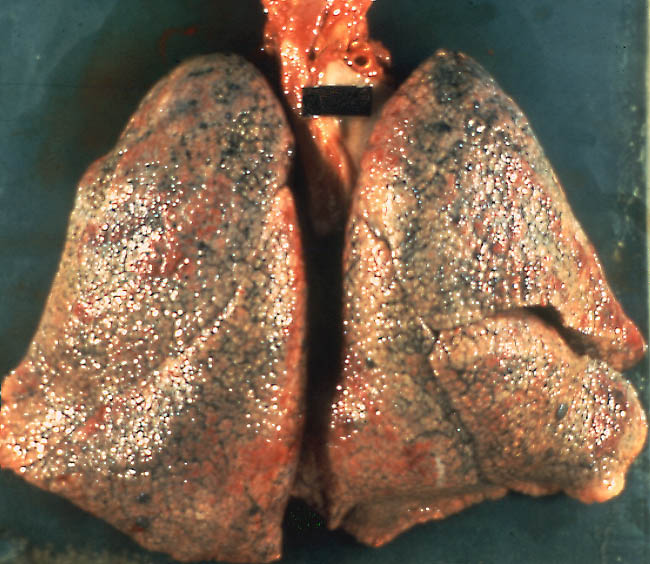

肺纖維化圖片

_重度肺纖維化的晚期